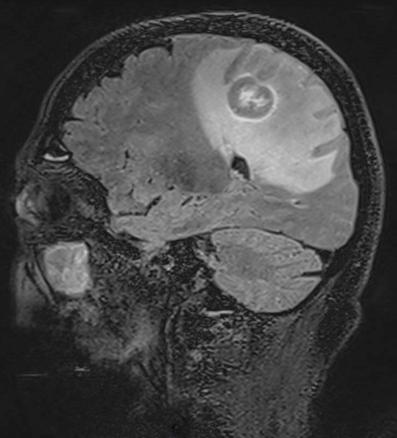

Le lymphome primitif du système nerveux central (SNC) est un lymphome non hodgkinien de haut grade.Il touche l’adulte entre 50 et 60 ans, immunodéprimé et immunocompétent.Le traitement associe chimiothérapie et radiothérapie cérébrale.